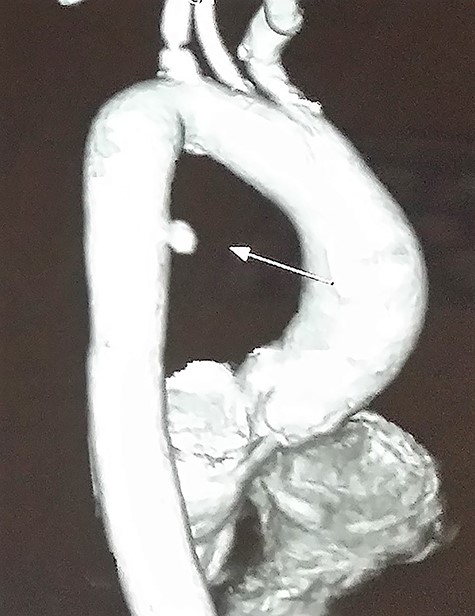

Ultrasound of abdomen and pelvis was normal. Upper gastrointestinal tract (UGI) endoscopy was done immediately, which revealed ulceration with a blood clot at 25 cm of the esophagus (Fig. 1).

UGI endoscopy, clot with underlying ulceration in the esophagus.